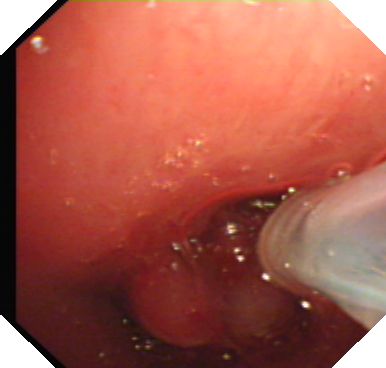

因患者长时间气管切开,气道内炎症严重,粘膜水肿明显,分泌物多,手术视野易受干扰,严重影响手术操作进程,经过1个半小时的不懈努力,气道内的肉芽组织基本清除,为避免肉芽组织继续生长,再经支气管镜使用冷冻治疗仪反复冷冻手术切口数次,达到使残余肉芽组织坏死的目的。

(冷冻治疗)